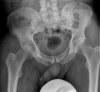

Pelvic AP view, Hip joint의 AP와 frog-lateral view를 촬영합니다.

초기에는 미세한 골감소증과 관절 삼출액이 나타나며 진행되면 관절간격 소실, 관절 주위 뼈 침식 소견이 나타납니다.

X-ray : 고관절 활액막염(Synovitis of the Hip)